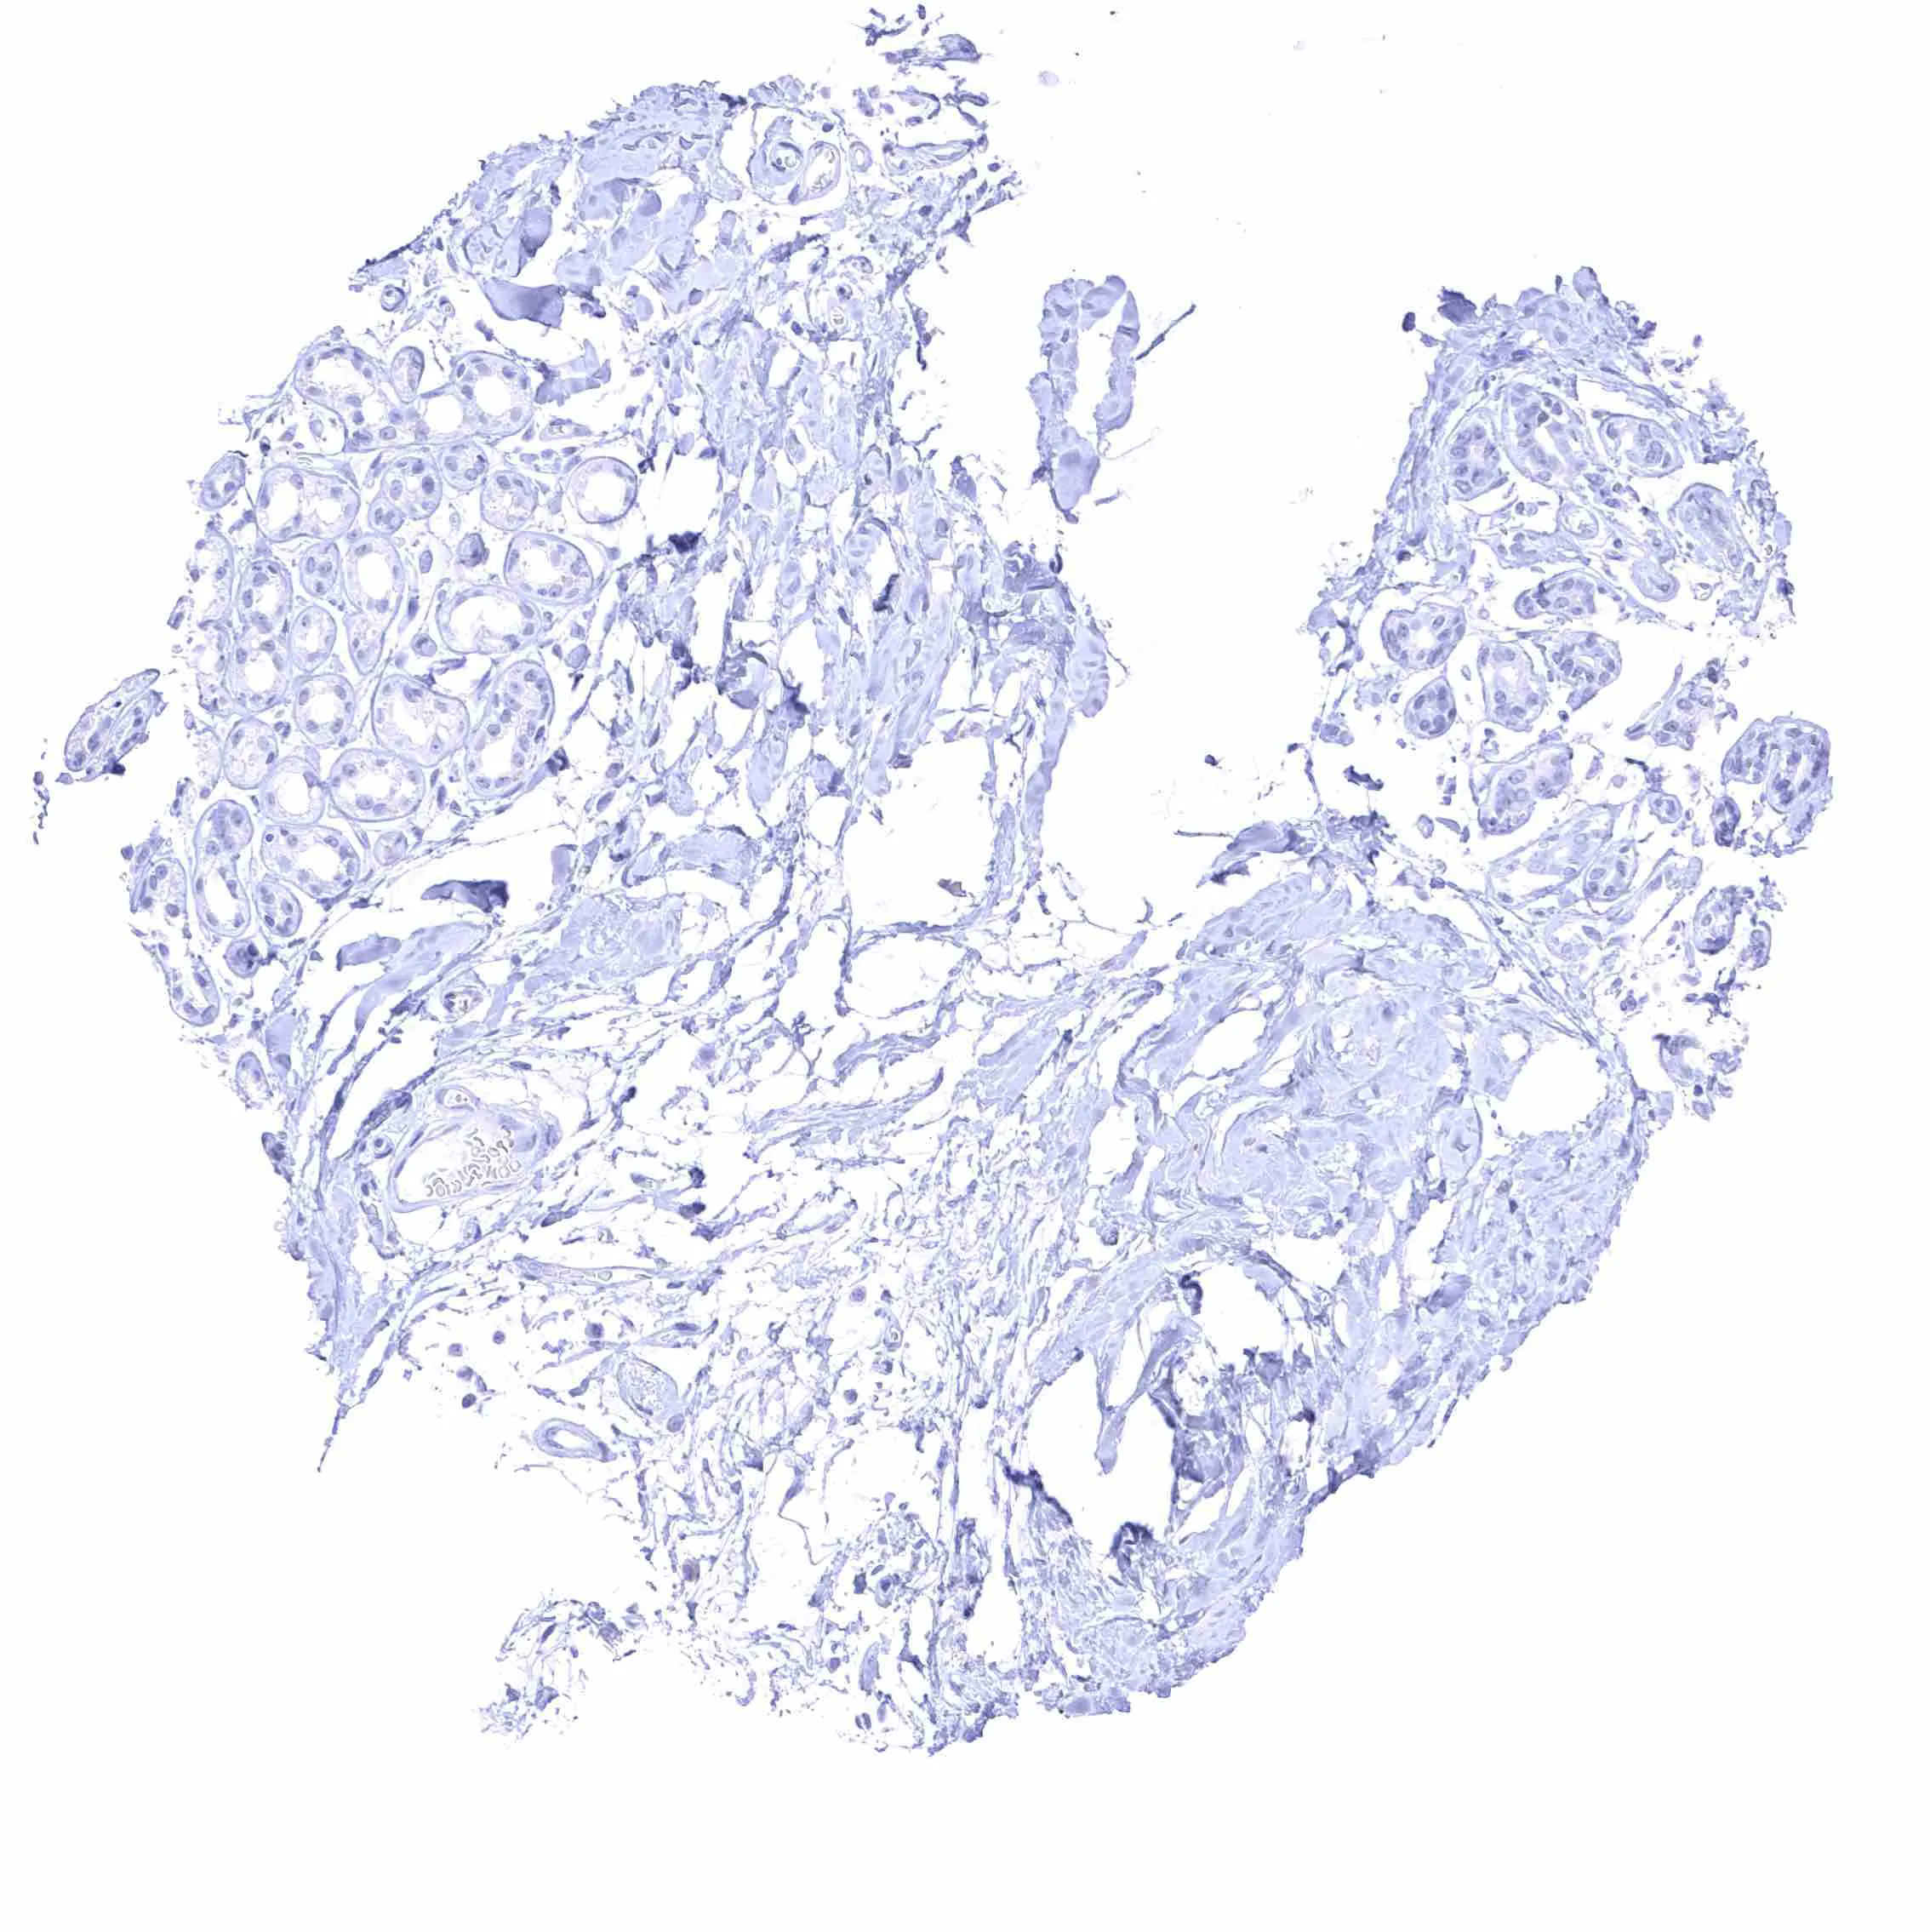

Placenta (amnion and chorion)

Placenta, early

Placenta, mature